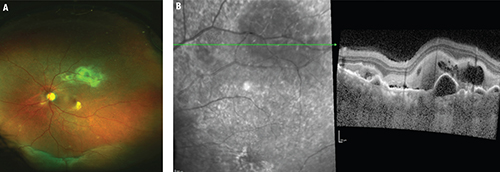

| Figure 1. On exam (A), this patient had an inferior retinal detachment, shallow submacular fluid associated with hard exudates and subretinal fibrosis. Creamy subretinal infiltrates along the superotemporal arcade were also visible. Optical coherence tomography (B) with a cut through the superotemporal arcade showed dilated choroidal vasculature, multiple pigment epithelial detachments and hyperreflective subretinal infiltration. |

OCT (Figure 1) demonstrated significant choroidal thickening with dilated choroidal vasculature, diffuse SRF extending inferiorly, multiple pigment epithelial detachments and hyperreflective subretinal infiltration under the superotemporal arcade. Fluorescein angiography imaging showed patchy choroidal filling followed by multiple hyperfluorescent points with late leakage and staining of subretinal fibrosis. No signs of vasculitis or papillitis were present.